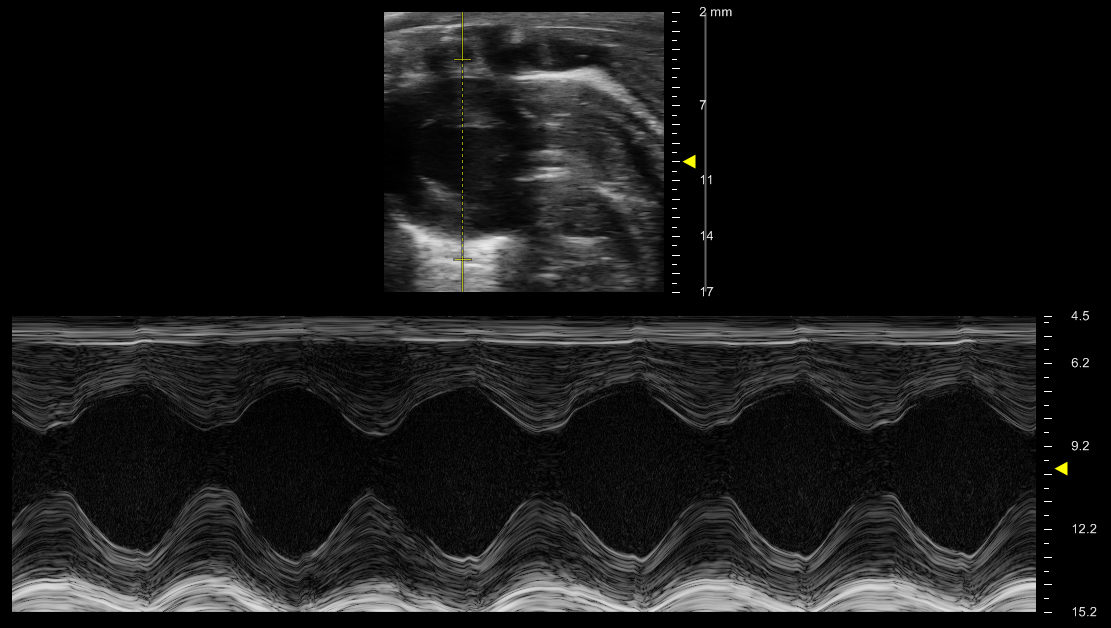

Heart - M Mode

M-mode examines a line of Motion over time. Using M-mode in echocardiography displays the movement of the myocardium allowing for accurate and real-time measurements of wall thickness, internal diameter, and heart rate. It is from these parameters that many systolic parameters are derived (i.e. fractional shortening, ejection fraction, chamber volumes, etc.).